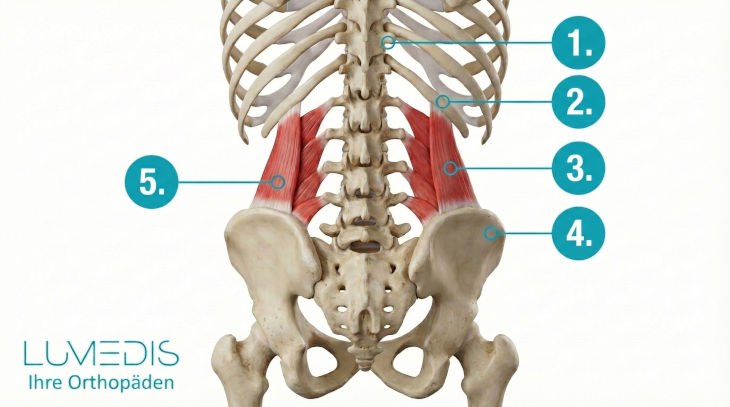

Anatomie der Rückenmuskulatur

Abbildung der Rückenstreckmuskulatur

M. quadratus lumborum